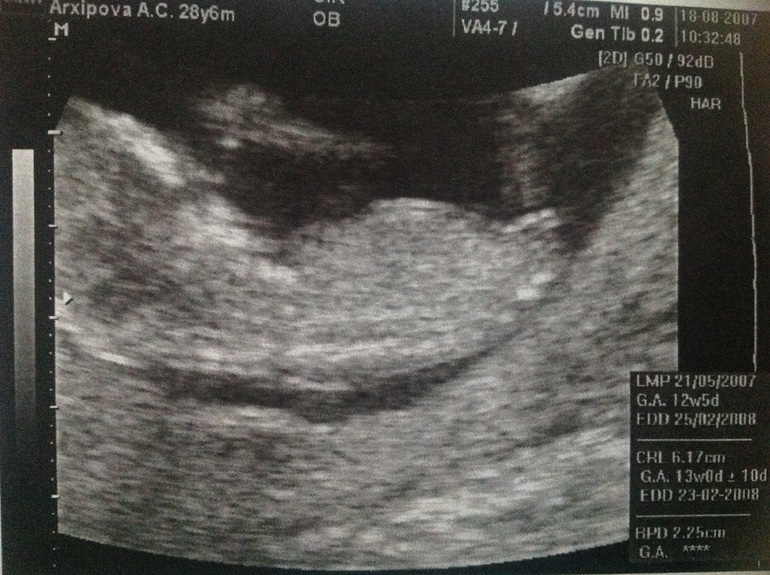

У нас в 12 недель ЧСС было 186!